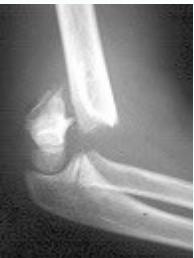

Case Example: 6-year-old girl, fell from swing

Initial injury